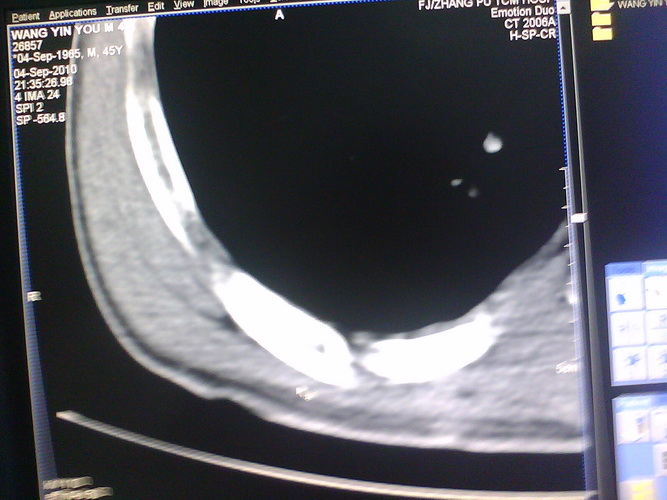

患者,男性,41y,外伤病号,来拍片,发现右侧第9后肋,肋骨膨大,有密度不均,想问大家,是否有问题,要考虑什么东西,谢谢

右侧第九后肋骨纤维结构不良。

考虑骨纤维异常增殖症(混合型)。

肋骨是骨纤好发部位。